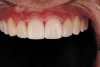

Nightguard Fabrication and Follow-up

An intraoral scan was taken and sent directly to the laboratory for express fabrication of a digitally designed 3D-printed nightguard. The patient was followed up 3 days later. During this appointment, the occlusal splint was delivered, and a digital occlusal analysis was performed with the patient seated upright to analyze an even occlusal force distribution. The mandibular teeth were whitened again to better match the final veneers (Figure 22 and Figure 23). Because the patient would be traveling for work for several weeks, he was issued a dental monitoring scan box to complete review scans as required to reassess the postoperative result.

Fig 22. Postoperative extraoral situation.

Figure 22

Fig 23. Postoperative intraoral situation.

Figure 23